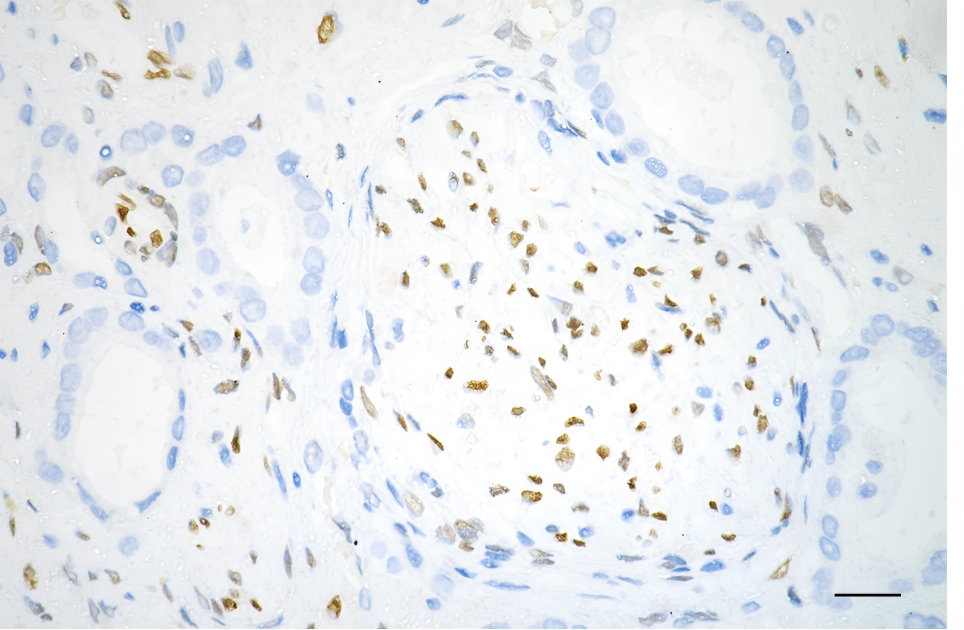

• Immunohistochemistry was performed on paraffin-embedded human prostatic adenocarcinoma using fibroblast growth factor 2 antibody. Antigen retrieval was done in sodium citrate buffer (pH 6.0). DAB was used for detection, with hematoxylin counterstaining. Images were acquired using a Nikon Ci-L Plus microscope (40× objective). Scale bar: 25 μm.